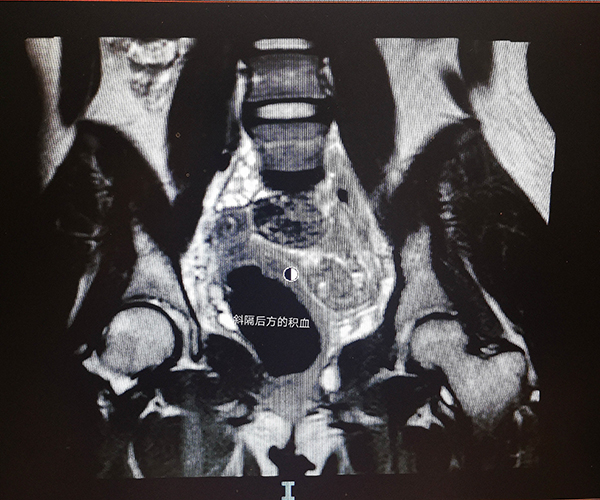

经过一番解释,妈妈和孩子对疾病有了了解,决定进行手术治疗。杨岚副主任医师对该类疾病有着丰富的临床经验,经过认真地查体和磁共振影像评估,她带领团队制定了周详的手术计划,最终成功为小龙实施了“阴道成形术+阴道斜隔切除术”。打开了封闭的隔墙,约500ml粘稠的积血“奔涌而出”,仔细“拆除”了围墙后,宫腔镜检查双侧宫颈形态和宫腔都恢复正常,手术取得了满意的效果。